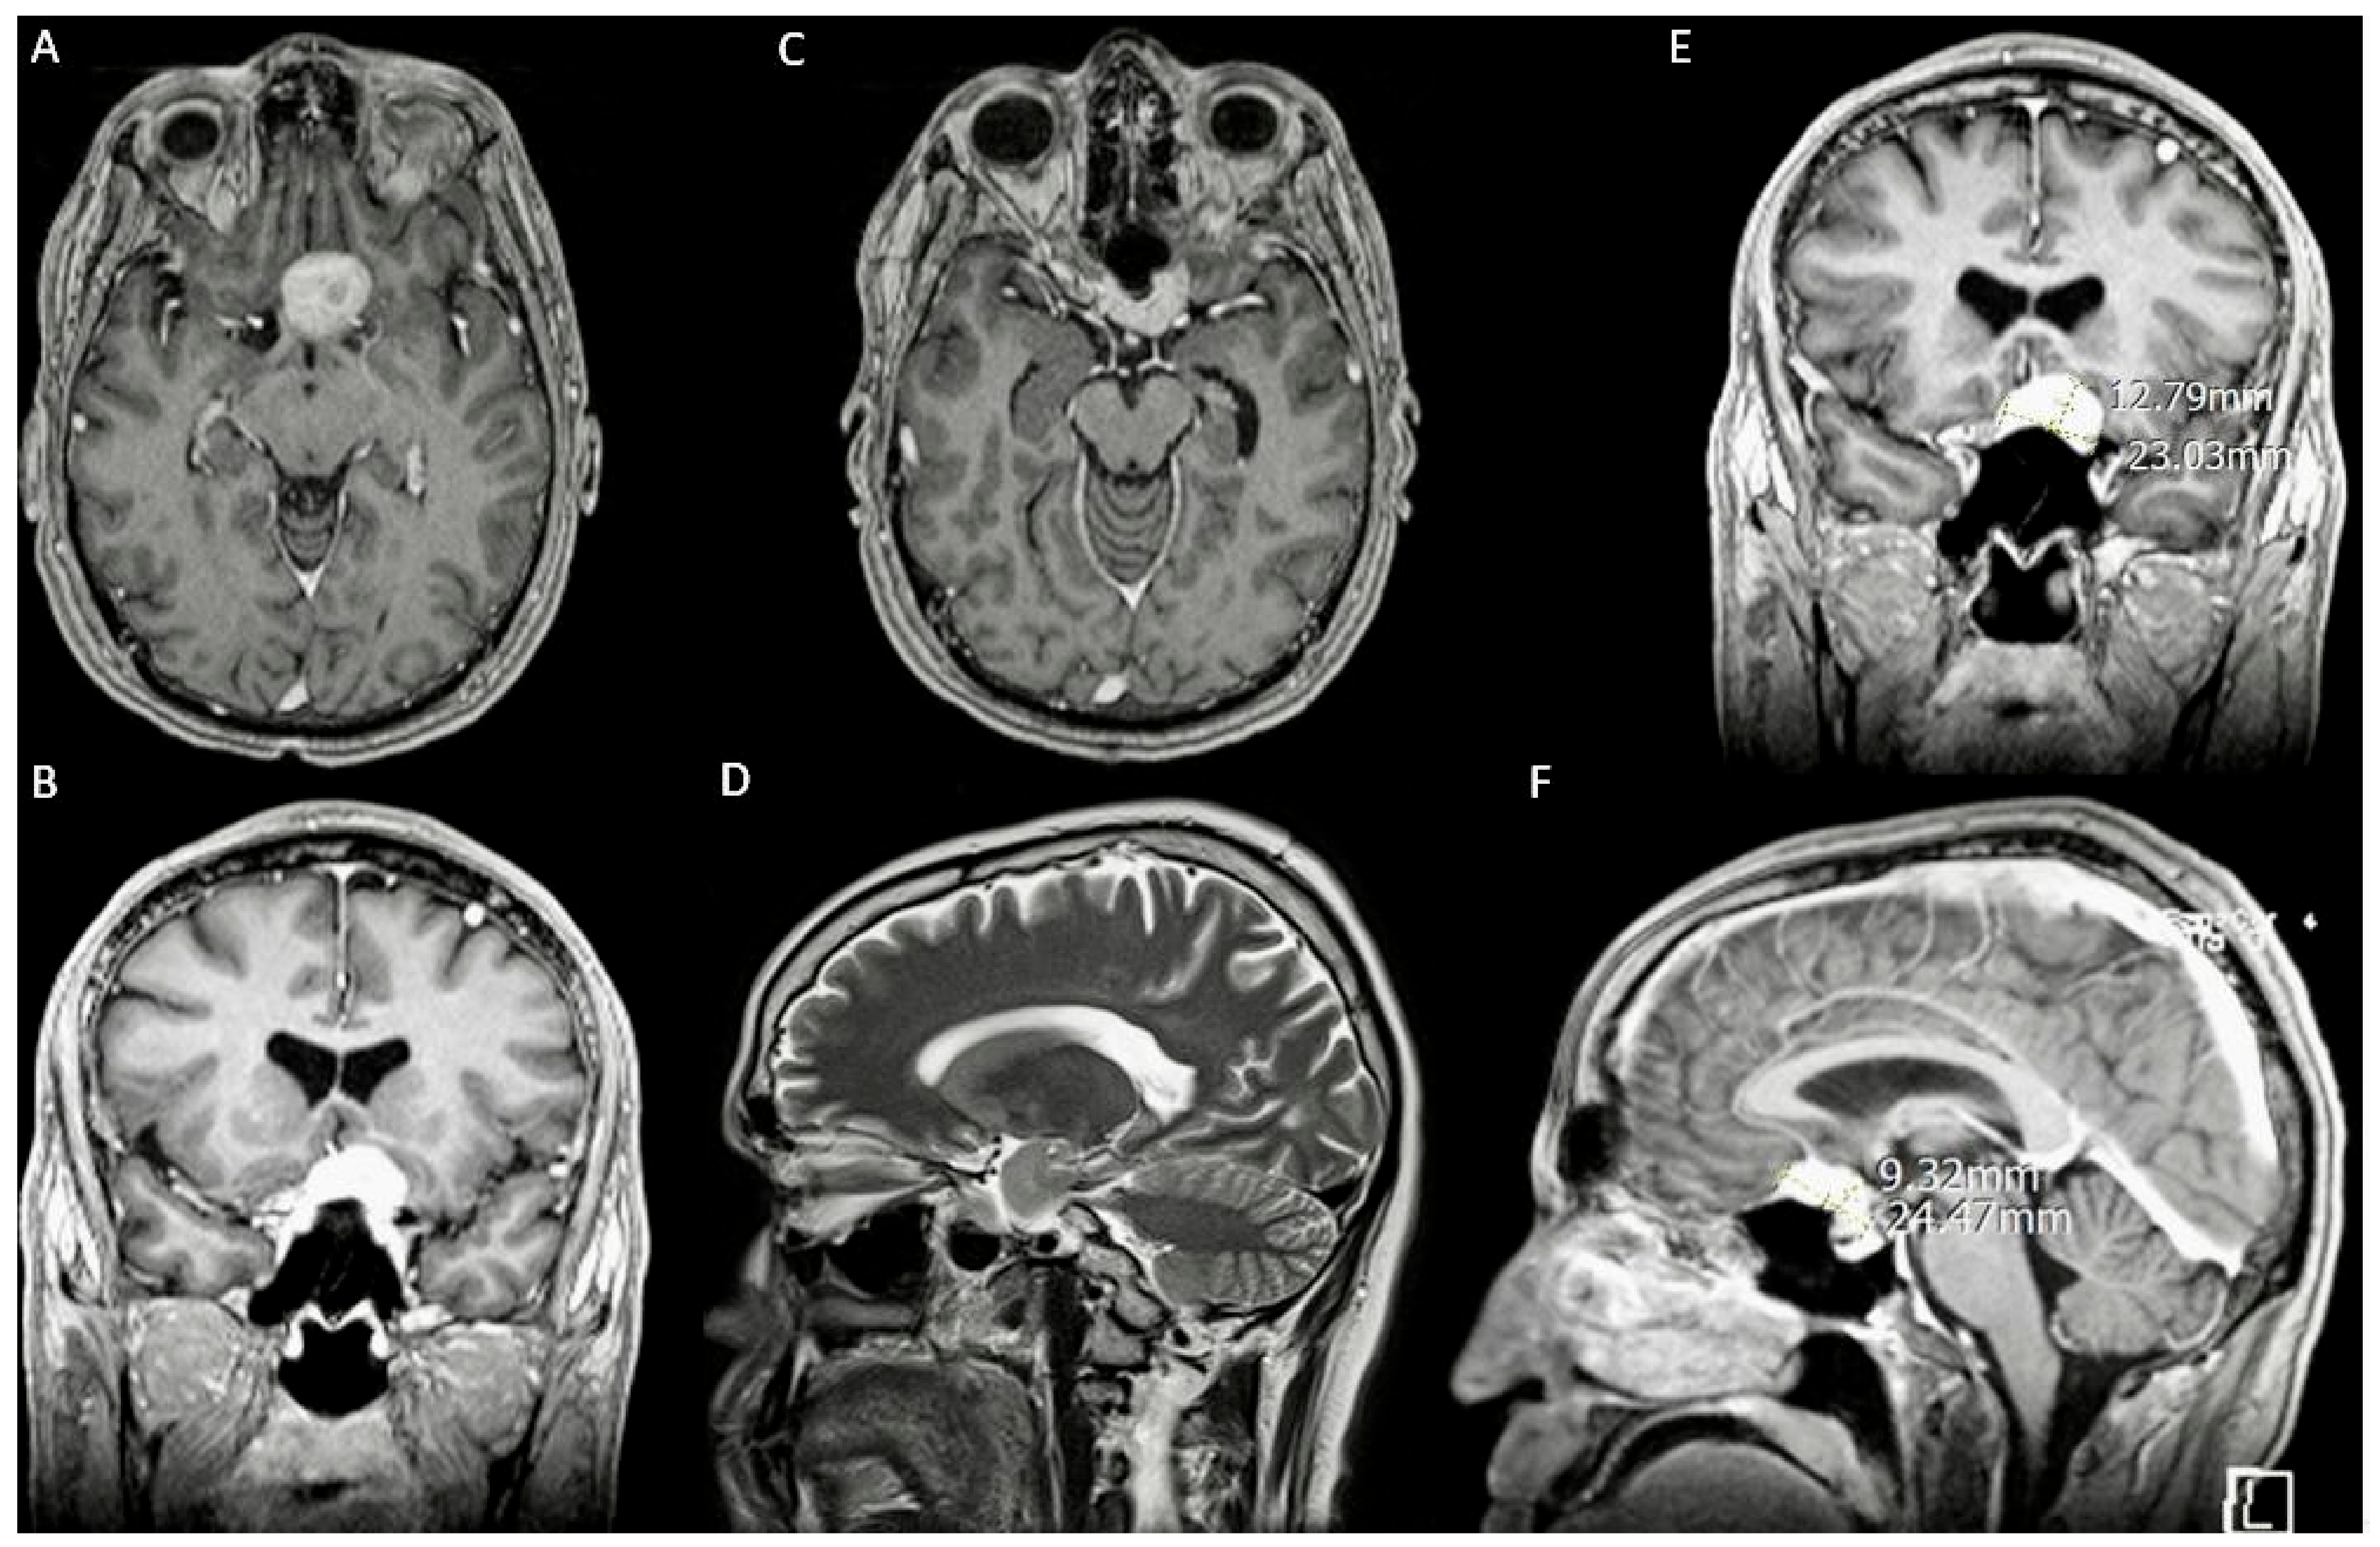

3.1. Case 1

3.1.1. Demography, Presentation, and Evaluation

3.1.2. Intervention

3.1.3. Postoperative Period